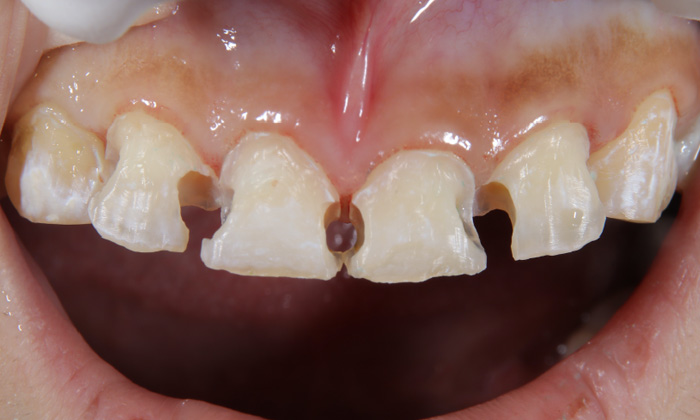

まずは悪くなっている歯質のみを削りました。写真からも分かるように、残せた健康な歯はたったこれだけしかありません。その後、直接法コンポジットレジン修復という、歯に直接素材を接着する方法を行いました。歯のすき間や表面を埋め、機能性や見た目を整えました。